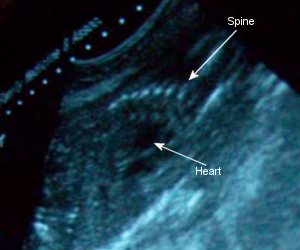

November 26th: I only gained 1 pound in two weeks, so I was now 138. She’s measuring well and my glucose was fine. I asked again to check if she’s a girl (yes, I won’t believe it till I see it!), but her little legs were too tightly crossed together. I did, however, get to see her spine and toes! Oh, and she’s already turned upside down! The earliest of all the kids (the other 3 turned over at exactly 28 weeks).

Sono Pic: